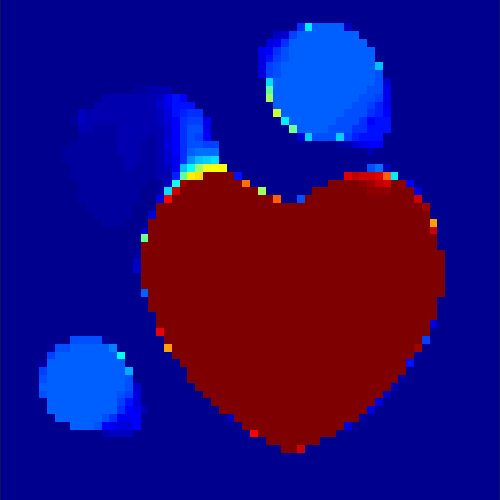

In a first test, every image sequence was reconstructed out of the exact given sinograms. Additionally we tested noise corrupted data by first scaling the sinogram by a parameter , corrupting them with Poisson noise via the MATLAB imaging toolbox command imnoise and finally rescaling the image to the original range (see figure 4). The average count number per time step (i.e. the average of the discrete -norm of the data at each time step) is approximately in case of the heart-shaped data set and ca. in case of the rat liver simulation. The results at a certain number of time steps can be seen in figure 6 and 7. For comparison, we additionally performed a reconstruction with a simple alternating EM method, keeping the assumption that the tracer can be modelled as a sum of indicator functions and subconcentration curves, but neglecting any regularization terms. In all tests, the outer iteration number was set to 1000 with 10000 inner iterations per subproblem, to obtain a result within a reasonable time period. As stopping criterion, we chose the primal dual residual (cp. [12]) for the inner and the maximum over the Frobenius norms of and for the outer iterations. The results are displayed in 6 and 7 respectively.

As one can see in both figures, the reconstruction method applied to each data set performs very well, especially in contrast to the simple alternating EM method. This clearly shows the benefits of the proposed regularization methods. In case of noise-free given data, the shape of every object, where especially the heart is of higher interest, is clearly defined. As expected, we often observe errors in the edges of each region and where two regions are directly connected (the heart and the upper left circle). This causes the algorithm to incorrectly assign these pixels to another region. Furthermore, the reconstruction difficulties increase with an increase in noise. Some more pixels are assigned to the wrong region, which leads to a small hole-like structure within the heart region and causes a slight blurring effect. In the second data set the method clearly outperforms several other approaches by providing very clearly defined regions and even reconstructing fine structures of the phantom. However, as mentioned before, a clear reconstruction of the rat liver required highly optimized parameter sets, which makes the whole problem quite susceptible to parameter changes.

Based on the sinogram data we applied the proposed algorithm in order to reconstruct the original image sequence. The results for both test cases are shown in figure 10.

As one can see, the method is able to reconstruct the regions properly, even in case of a low count number. Within a number of iterations (average of 100 outer and 10000 inner iterations), the algorithm presents a reasonable reconstruction of the region of interest and the corresponding regional tracer concentration curves. Here, the parameters were not optimized as in the case of the synthesized data sets in the previous section, but kept fixed as , and . With futher optimized parameter values one could possibly provide even better results.